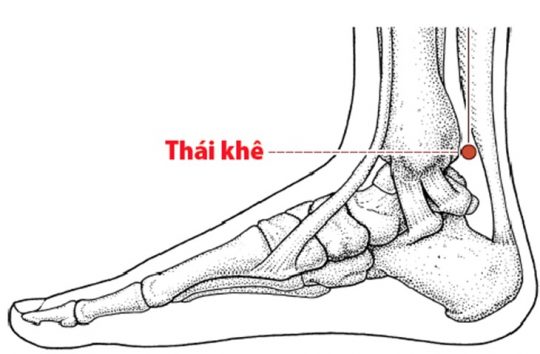

3. Huyệt Thái Khê: Day bấm huyệt này khi bị ù tai kéo dài hoặc cơ thể mệt mỏi lâu ngày, phù hợp với người lớn tuổi, người gầy yếu hoặc người bị ù tai âm ỉ, nghe kém dần.

– Vị trí: Nằm ở mặt trong cổ chân, trong khe lõm giữa mắt cá chân trong và gân gót chân.

– Tác dụng: Theo y học cổ truyền, huyệt Thái Khê có tác dụng hỗ trợ chức năng của thận — cơ quan liên quan đến tai và thính lực — từ đó giúp cải thiện tình trạng ù tai kéo dài.

– Cách thực hiện: Day ấn nhẹ từng bên trong 1–2 phút, lực vừa phải.

Vị trí huyệt Thái Khê.